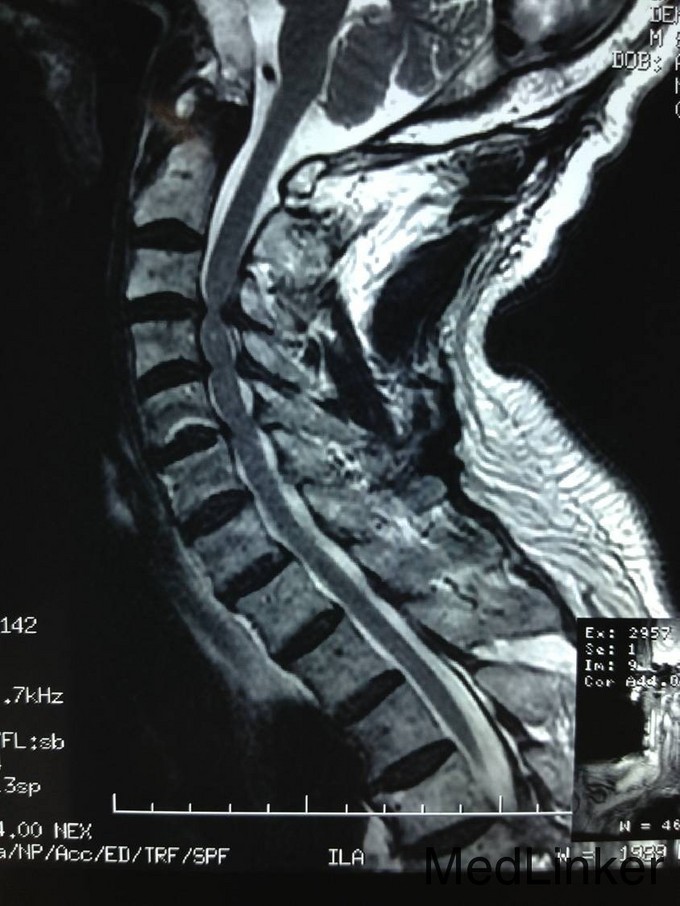

患者男,81岁,自述于1个月前出现双上肢感觉减退,发胀,以左侧为重,后来加重,左侧握力减退,于201医院就诊,行颈椎MR检查,提示为颈3-4、4-5间盘突出,为求进一步治疗就诊于我院,患者病来饮食、睡眠佳。大小便正常,体重无明显变化。

颈椎生理弯曲消失,活动度正常。双上肢感觉减退。双手握力(R5级,L4级),伸肘肌力(R5级,L5级),屈肘肌力(R5级,L5级),Hoffman(R-,L+)桡动脉搏动有力,末梢血运良。

诊断:颈椎病,颈椎间突出,高血压病 患者入院后完善相关检查,请相关科室及麻醉科会诊,医院医务部审批后,查无其他手术禁忌症,于全麻下行颈椎后路单开门椎管扩大减压侧块螺钉内固定术。术后给予患肢雾化祛痰,抗炎,消肿,营养神经,接骨等对症治疗。术后患者在颈领的保护下可下地行走,术后14天拆线后予以出院,